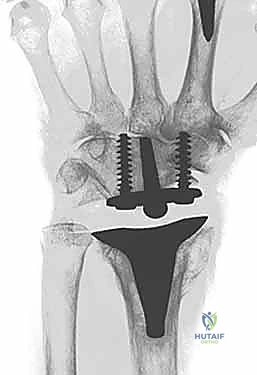

The evolution of modern implant design has capitalized on modularity, superior tribology, and improved anatomic geometries to provide enhanced longevity. A great debt of gratitude is owed to Dr. Jay Menon for popularizing stable distal screw fixation into the carpus, fundamentally altering the biomechanical paradigm by avoiding the destructive lever arm created by a long intramedullary stem inserted into the third metacarpal. Today, the three most popular wrist designs utilized in the United States are the Universal 2 (KMI/Integra), the Re-Motion (Small Bone Innovations [SBI]), and the Maestro (Biomet). The Universal 2 Total Wrist prosthesis, an improved version of Dr. Menon's original design, utilizes a flat carpal cut, screw fixation distally into both the second metacarpal and hamate, and a modular, distally based polyethylene cap that articulates with a proximal cobalt chrome radial component.

Normal anatomic parameters of the distal radial articular surface include a volar tilt of approximately 11 degrees and a radial inclination of 22 degrees. Recreating these spatial relationships is a fundamental goal of modern implant systems. The Re-Motion Total Wrist, for instance, is fundamentally designed to resurface the distal radius while allowing about 15 degrees of intended "wiggle" or toggle built into the snap fit of the polyethylene cap with the carpal plate, compensating for minor kinematic mismatches. Conversely, the Maestro Wrist utilizes a metal convex component articulating with a concave polyethylene component, mimicking successful total hip and shoulder designs, and features a modular titanium stem designed to achieve diaphyseal fill and rotational stability.

The sigmoid notch of the distal radius provides the articulation for the DRUJ. Strong dorsal and palmar radioulnar ligaments provide critical DRUJ stability. While earlier designs like the Re-Motion made no specific attempt to preserve the DRUJ, modern iterations and systems like the Universal 2 and Maestro feature instrumentation and radial component geometries specifically designed to preserve the DRUJ and the ulnar head. In cases where the DRUJ is irreparably damaged, many wrist replacements are performed in conjunction with ulnar head replacement arthroplasty or a Darrach procedure, though preservation of the ulnar head is always preferred to maintain the ulnocarpal ligamentous complex and provide a buttress against ulnar translation.

Following capitate reaming, the chosen carpal plate and stem are assembled and inserted into the capitate and seated onto the resected carpal surface. The carpal plate is anchored to the carpus with a radial screw that optimally does not penetrate the second metacarpal, and a second screw placed ulnarly into the hamate. This construct ensures stable distal fixation while avoiding the deleterious lever arm of a long metacarpal stem. Trial reductions are performed to assess stability, range of motion, and impingement. Once kinematics are confirmed, the definitive ultra-high-molecular-weight polyethylene (UHMWPE) body—which is direct compression molded onto a cobalt chrome alloy radial body—is impacted. The capsule and extensor retinaculum are meticulously repaired to prevent extensor tendon bowstringing and provide a robust soft tissue envelope over the implant.

Biomechanical studies have definitively validated the paradigm shift away from metacarpal intramedullary stems. Finite element analysis and cadaveric kinematic studies have shown that distal screw fixation into the carpus, combined with a broad carpal plate, more evenly distributes compressive loads across the midcarpal joint and vastly reduces the shear forces that lead to early osteolysis. Furthermore, comparative cohort studies have repeatedly demonstrated that patients who undergo TWA report higher satisfaction rates and better ability to perform personal hygiene tasks compared to matched cohorts undergoing total wrist arthrodesis.

Clinical & Radiographic Imaging Archive